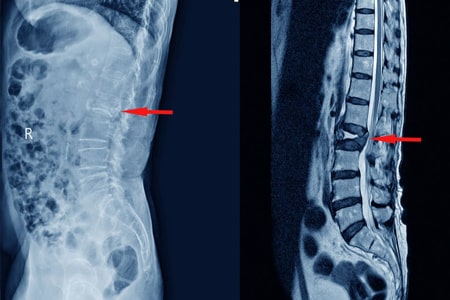

Tratamientos conservadores en el tratamiento de las fracturas vertebrales por compresión con dolor agudo : revisión sistemática y metanálisis en red

Los AINE y la teriparatida pueden ser las opciones de tratamiento preferidas para el tratamiento del dolor agudo en las fracturas vertebrales por compresión osteoporóticas. Aunque la calcitonina también demostró ser beneficiosa, su perfil de seguridad y los posibles efectos adversos restringen su aplicación generalizada. La evidencia limitada sobre los aparatos ortopédicos y los analgésicos subraya la necesidad urgente de investigaciones futuras. JAMA Netw Open. 3 de septiembre de 2024